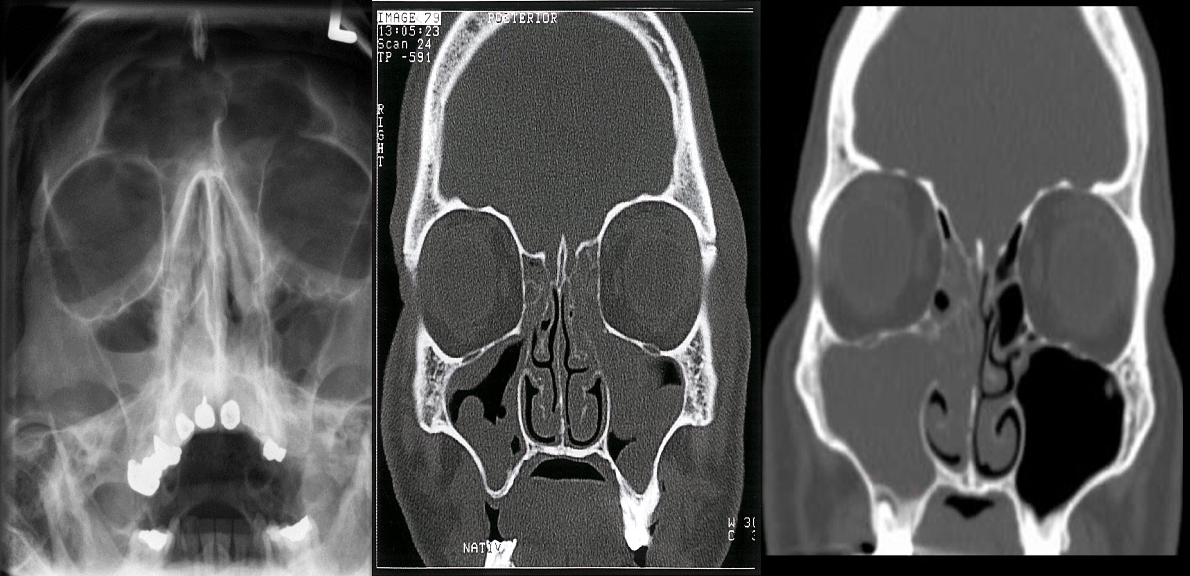

A) X-ray of the paranasal sinuses

- An air-fluid level is visible within the right maxillary sinus

- This is a typical radiological feature of sinusitis.

B) Chronic rhinosinusitis CT paranasal sinuses (without contrast; coronal plane) The ethmoid sinuses are opacified and there is lobulated thickening of the walls of the maxillary sinuses. The findings indicate nasal polyps and retention cysts.

C) CT paranasal sinuses (coronal plane) of a patient with acute sinusitis The right maxillary sinus is completely opacified. Extensive soft tissue density material is also present in the ipsilateral nasal cavity and the right ethmoid sinus is nearly completely opacified.